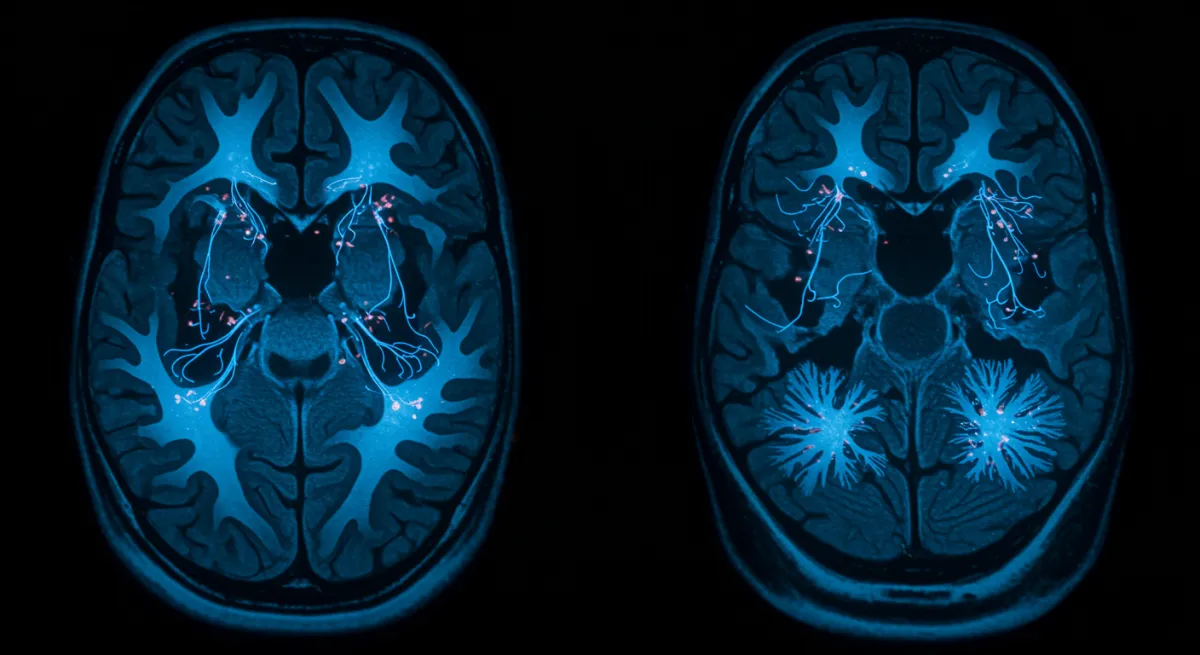

Neuroimaging studies consistently demonstrate that loneliness alters brain activity and structure across multiple networks. The “social brain” - including regions like the anterior cingulate cortex, insula, and temporoparietal junction - shows altered connectivity patterns in lonely individuals. These changes affect how the brain processes social information, regulates emotions, and responds to stress.

Loneliness activates the brain’s threat detection systems while suppressing social reward circuits. The anterior cingulate cortex becomes hyperactive to social threats, while the ventral striatum shows reduced response to social rewards. This creates a neurobiological state of hypervigilance combined with reduced motivation for social connection - a pattern that can become self-perpetuating.

Key findings from loneliness neuroscience research:

- Increased amygdala reactivity to social threats in lonely individuals

- Reduced prefrontal cortex activity during social cognition tasks

- Altered default mode network connectivity affecting self-referential thinking

- Decreased social reward network activity reducing motivation for connection

- Structural brain changes in regions involved in social processing with chronic loneliness